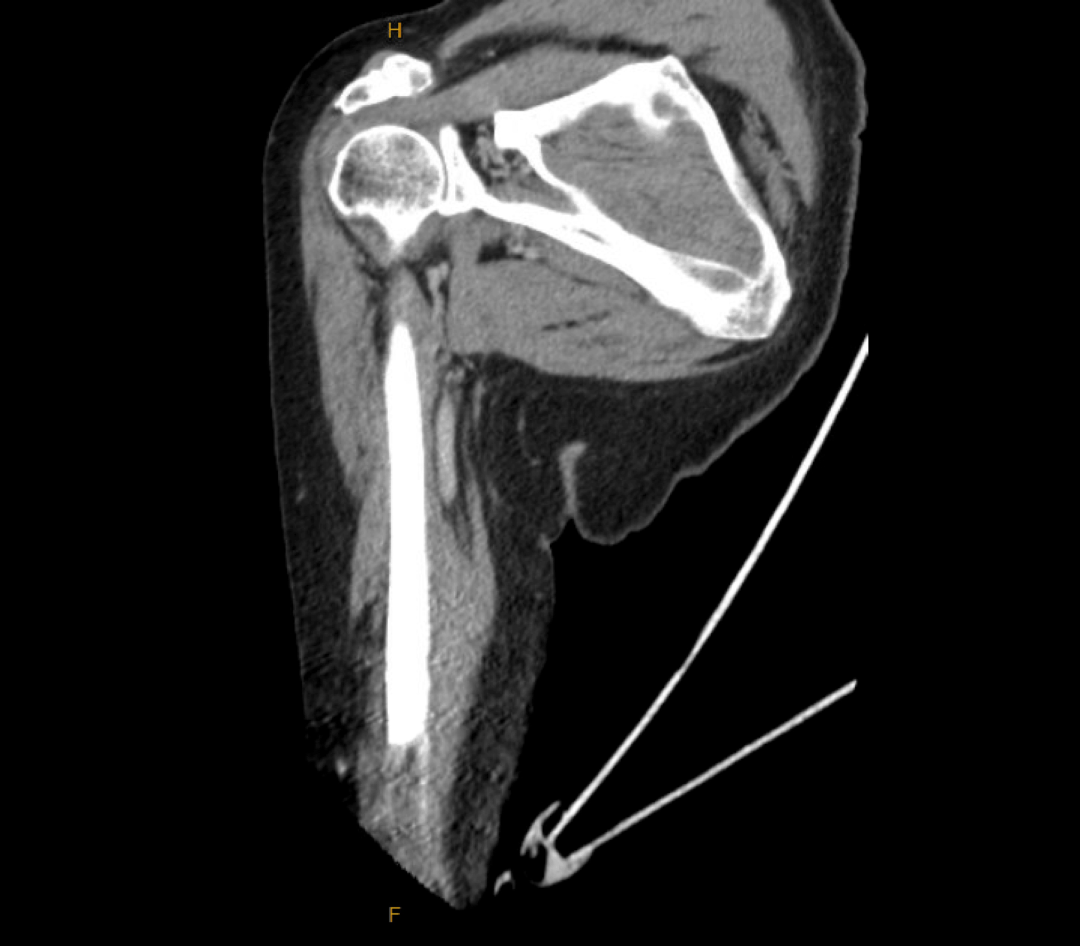

影像学检查:右侧肱骨、前臂增强CT(图1-图3)及左手X线摄片(图4)未见急性结构性或血管性病变;左手广泛存在退行性改变。

图2 右肱骨冠状位CT骨窗成像与Ⅳ对比右肱骨冠状位CT骨窗成像(Ⅳ造影)

图3 右肱骨冠状位CT软组织窗图像(Ⅳ造影)